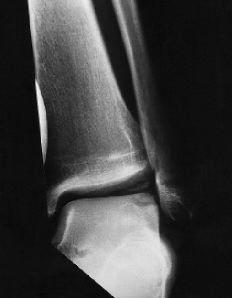

En los 64 pacientes se pudo realizar el diagnóstico en 63 casos mediante radiografías del tobillo, predominando las zonas claras (56%) y observando cuerpos libres en sólo tres ocasiones (5%) (Fig. 2). En la radiología postoperatoria se observaron dos datos interesantes; el primero es que en 18 casos (28%) había ausencia de lesión osteocondral en la fase de seguimiento, mientras en los demás existía bien una zona clara (19 casos) o irregularidades en el contorno articular con depresiones o impresiones de ésta (24 casos) (Fig. 3). En 16 casos se realizó una RM y en cuatro se realizó una TAC. El objeto de estas exploraciones fue el obtener más información sobre el estado de la lesión, con excepción del mencionado caso en el que radiográficamente no se pudo ver la existencia de dicha lesión y cuyo diagnóstico se hizo a través de la RM.

En cuanto al pronóstico del tratamiento quirúrgico de estas lesiones hay que señalar que cuanto más avanzada sea la edad del paciente o el grado de la lesión según la clasificación intraoperatoria peores serán los resultados finales (Fig. 7). La localización desempeña también un papel importante, siendo las lesiones laterales, en su mayoría ventrales (fuera de la zona habitual de carga), las que presentan un mejor pronóstico.

ABCFigura 7. Paciente de 11 años de edad. A: Rx preoperatorias. B: RM. Radiológicamente se consideró un Grado 3 a 4 de lesión. Intraoperatoriamente se encontró un reblandecimiento del cartílago, demarcado y sin fisuras. Se hizo una perforación retrógrada bajo control radiográfico y artroscópico. C: Resultado final tras 3 años de seguimiento; la paciente está asintomática.